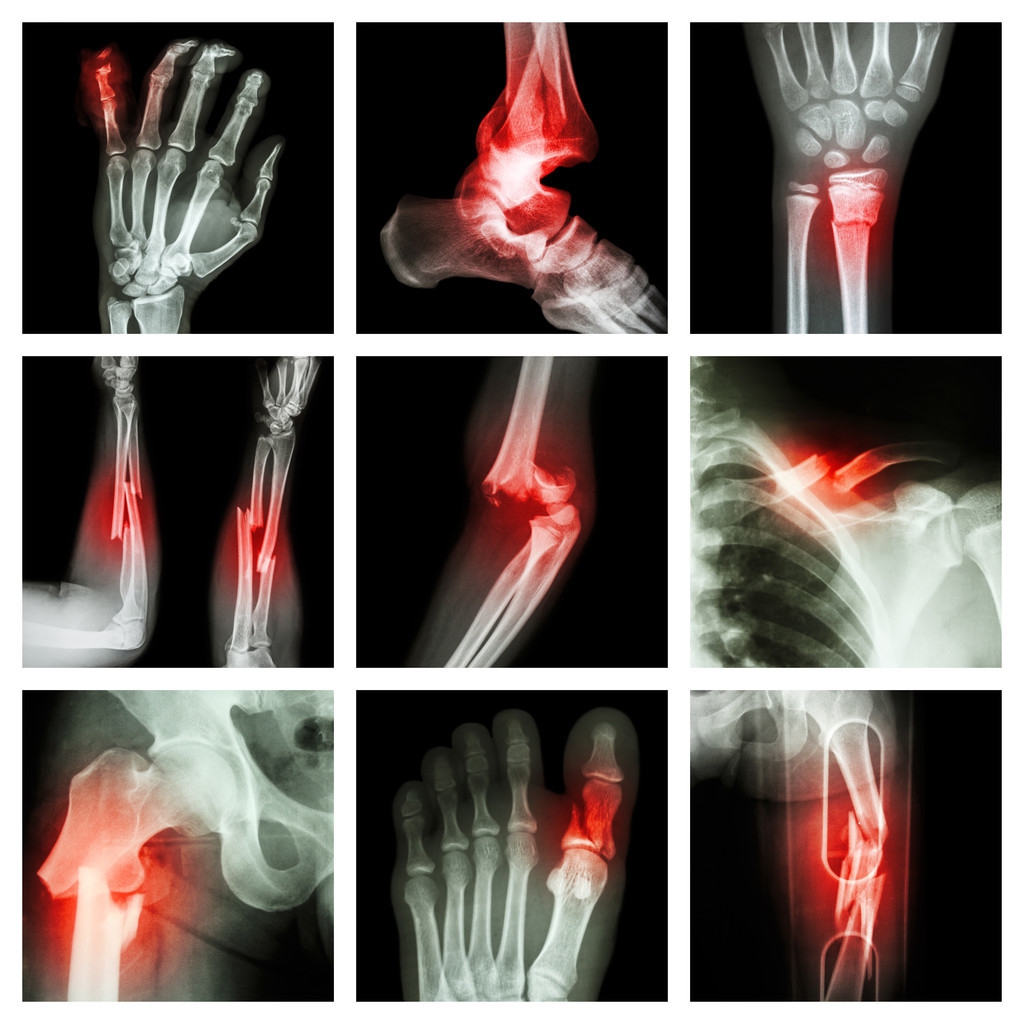

骨折是指骨结构的连续性完全或部分断裂。多见于儿童及老年人,中青年人也时有发生。病人常为—个部位骨折,少数为多发性骨折。经及时恰当处理,多数病人能恢复原来的功能,少数病人可遗留有不同程度的后遗症。